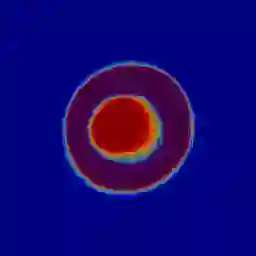

Manual medical image segmentation is subjective and suffers from annotator-related bias, which can be mimicked or amplified by deep learning methods. Recently, researchers have suggested that such bias is the combination of the annotator preference and stochastic error, which are modeled by convolution blocks located after decoder and pixel-wise independent Gaussian distribution, respectively. It is unlikely that convolution blocks can effectively model the varying degrees of preference at the full resolution level. Additionally, the independent pixel-wise Gaussian distribution disregards pixel correlations, leading to a discontinuous boundary. This paper proposes a Transformer-based Annotation Bias-aware (TAB) medical image segmentation model, which tackles the annotator-related bias via modeling annotator preference and stochastic errors. TAB employs the Transformer with learnable queries to extract the different preference-focused features. This enables TAB to produce segmentation with various preferences simultaneously using a single segmentation head. Moreover, TAB takes the multivariant normal distribution assumption that models pixel correlations, and learns the annotation distribution to disentangle the stochastic error. We evaluated our TAB on an OD/OC segmentation benchmark annotated by six annotators. Our results suggest that TAB outperforms existing medical image segmentation models which take into account the annotator-related bias.